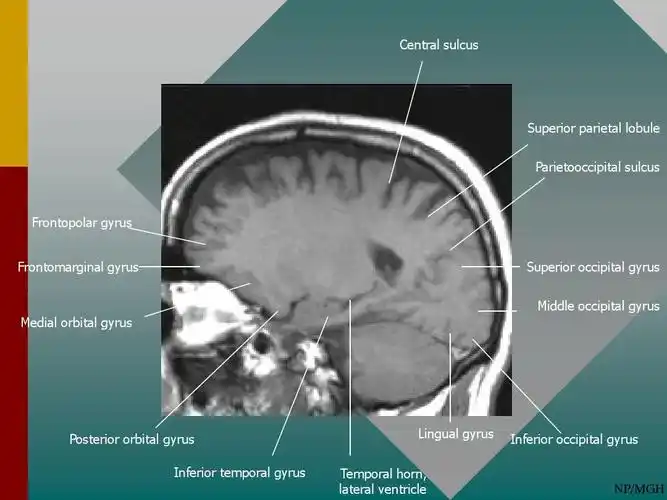

正常神经系统解剖(mri)ppt